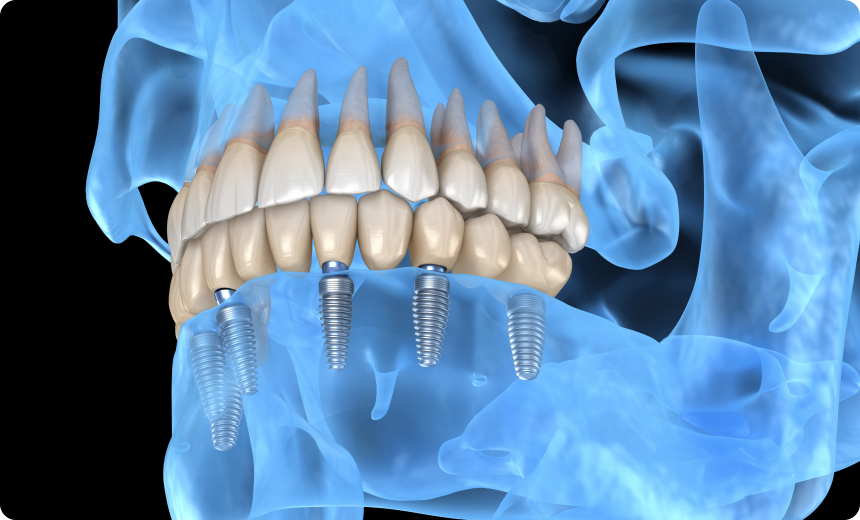

Le concept All-on-6 est une technique de réhabilitation dentaire qui consiste à poser une prothèse fixe sur six implants insérés dans la mâchoire. Cette méthode permet de remplacer toutes les dents d’une arcade dentaire lorsqu’elles sont absentes ou irrécupérables.

Le principe repose sur la répartition équilibrée de six implants stratégiquement positionnés dans l’os maxillaire ou mandibulaire. Cette répartition permet de soutenir une prothèse complète, tout en limitant le nombre d’implants nécessaires par rapport à une reconstruction traditionnelle qui en demande souvent plus.

Sous anesthésie locale, les six implants sont insérés dans l’os. Leur position est calculée pour supporter efficacement la future prothèse. La chirurgie dure généralement quelques heures et peut parfois être réalisée en une seule séance.

Le All-on-4 repose sur la pose de quatre implants pour soutenir une arcade complète. Le All-on-6 en utilise deux de plus, ce qui assure une répartition plus homogène des forces masticatoires. Cette différence rend la solution All-on-6 particulièrement adaptée aux patients ayant une densité osseuse suffisante et recherchant une stabilité renforcée.